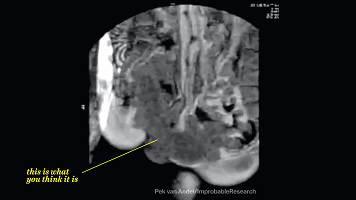

亲都亲完了这时候就要进入正题了

下面这个图就是啪啪啪的关键过程了

这时候我们的血液流动会重新分配

血液会在短时间内聚集在体表,导致

皮下毛细血管血流更加丰富,这使你的皮肤

表面敏感度和感受比平时更加明显,肌肉开始

从不规律性收缩转向为有规律的收缩